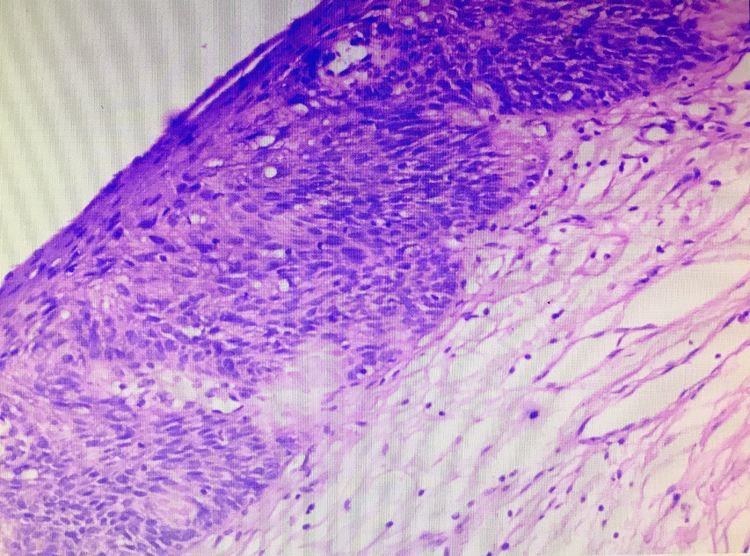

术后病理示:食管黏膜原位癌

术后病理示:食管黏膜高级别上皮内瘤变

讨论:两例患者的食管病变仅表现为局部发红、黏膜粗糙,白光内镜下不易识别,容易漏诊,经卢戈碘染色及NBI放大内镜观察,病变及范围显示较清晰。两例食管早癌首先在白光下被及时发现,联合卢戈碘染色及NBI放大内镜精细观察,病变及范围显示较清晰,及时行内镜下ESD术,对病变进行及时有效的治疗,术后病理提示基底切缘干净,为临床治愈性切除。